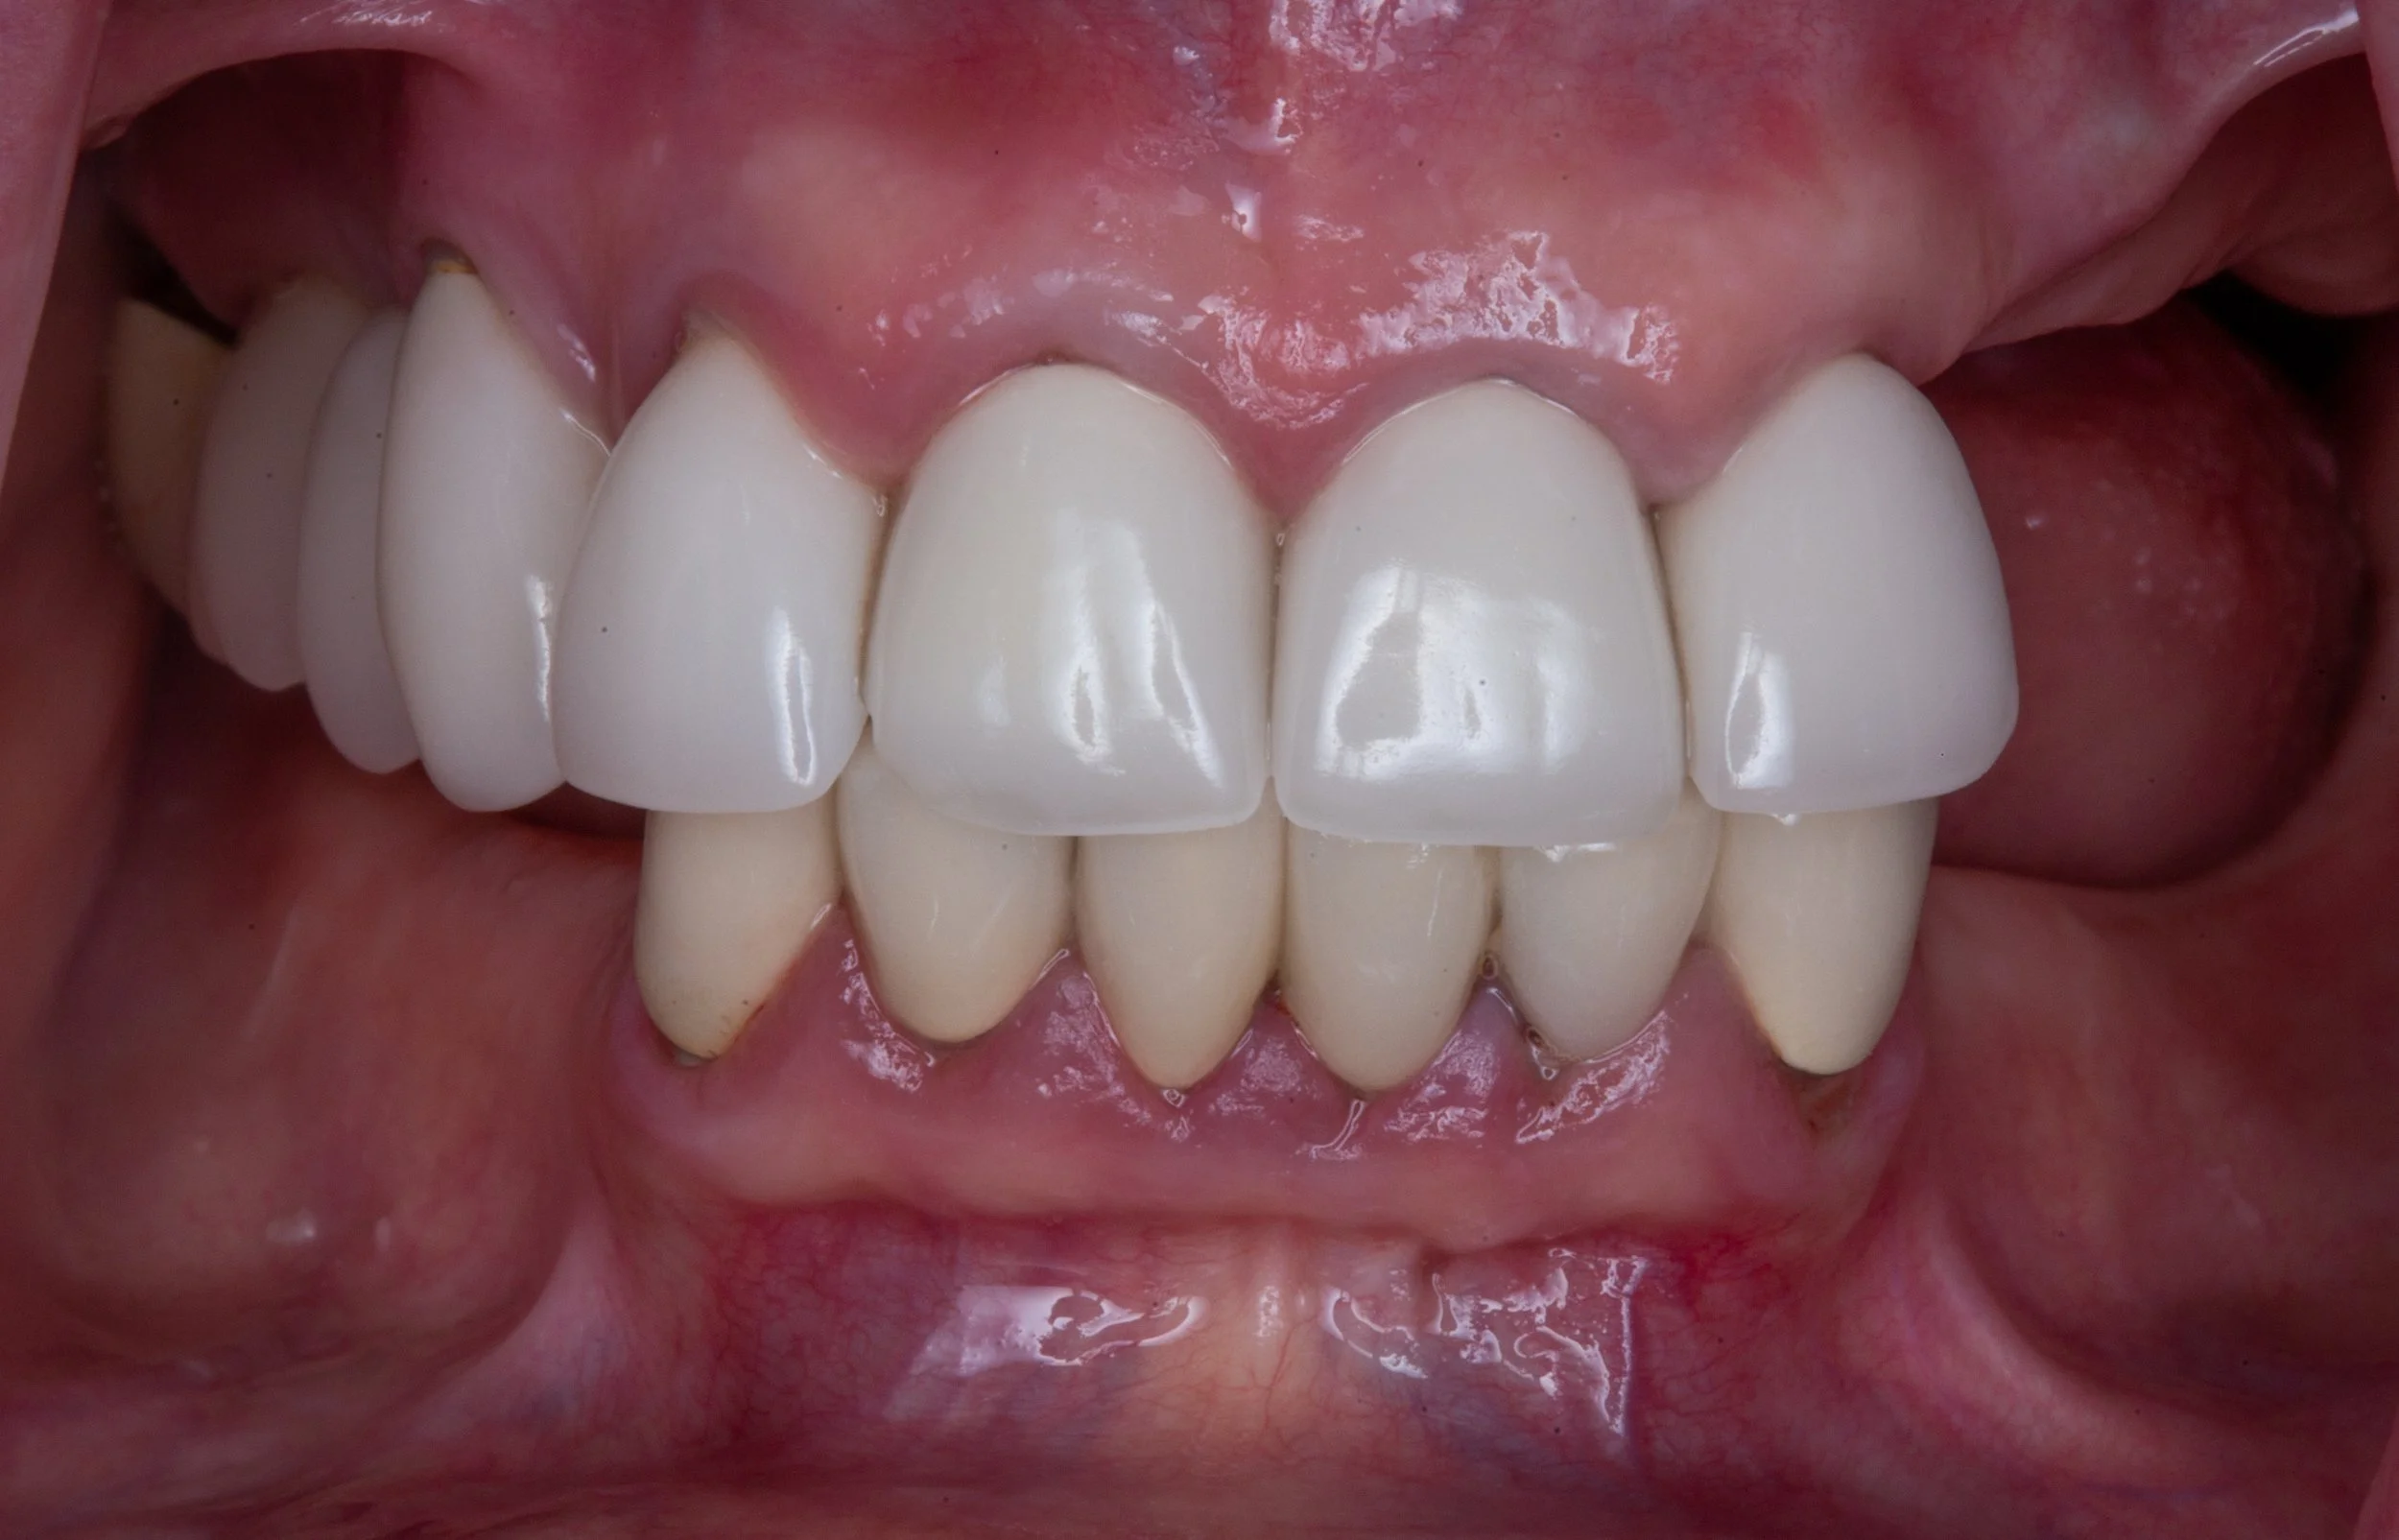

Replacing all of the upper or lower teeth with dental implants requires a high level of knowledge and coordination to ensure a successful outcome.

Learn how our comprehensive approach and access to multiple specialists distinguishes our team amongst others when performing complex smile rejuvenations.